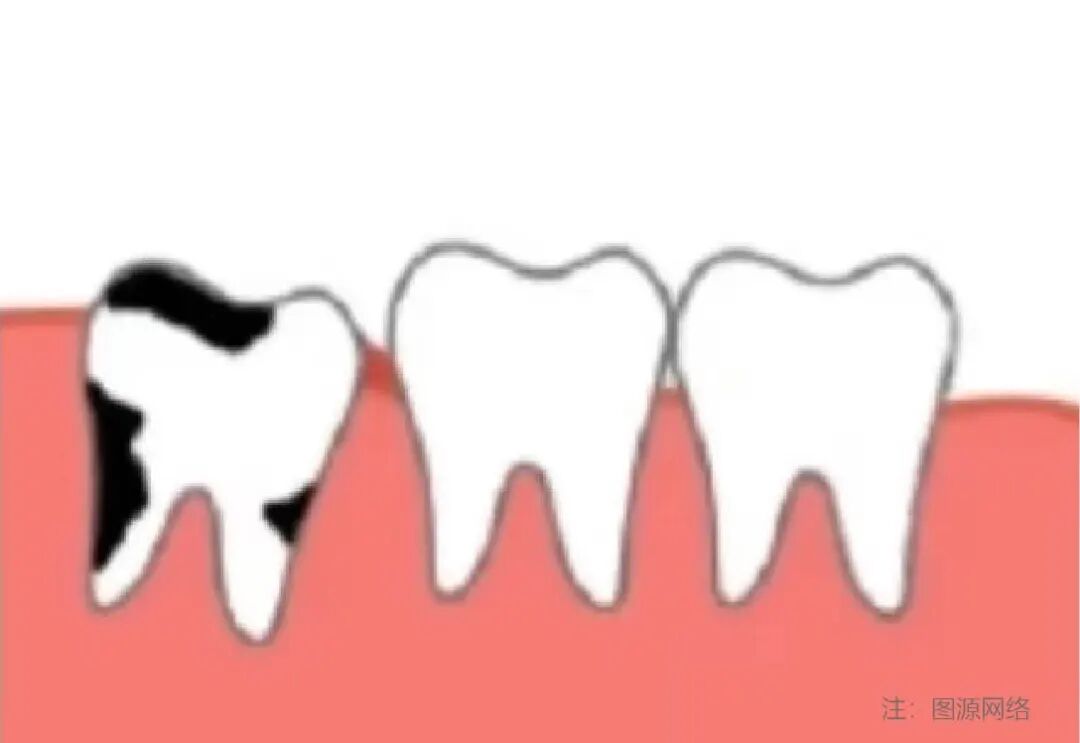

3)龋坏:智齿不易清洁,容易龋坏